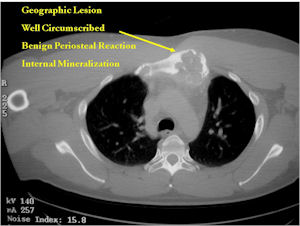

- Geographic, circumscribed lesion usually around 5cm in size.

- There may be expansion of bone, cortical thinning and cortical breakthrough. A soft tissue mass may accompany this lesion but the soft tissue component is usually contained by the periosteum.

- The periosteum remains intact around the soft tissue component. Might need a CT scan to detect the subtle calcification (Egg Shell Rim of Calcification) associated with an intact periosteal reaction

- The lesion may be entirely radiolucent but usually shows some degree of mineralization. Mineralization may appear stippled like cartilage but do not see chondroid pathologically. Mineralization is sometimes better detected on a CT scan rather than an x-ray.

CT Scan:

- More useful for detecting mineralization and evaluating extent of bone destruction than plain X-ray